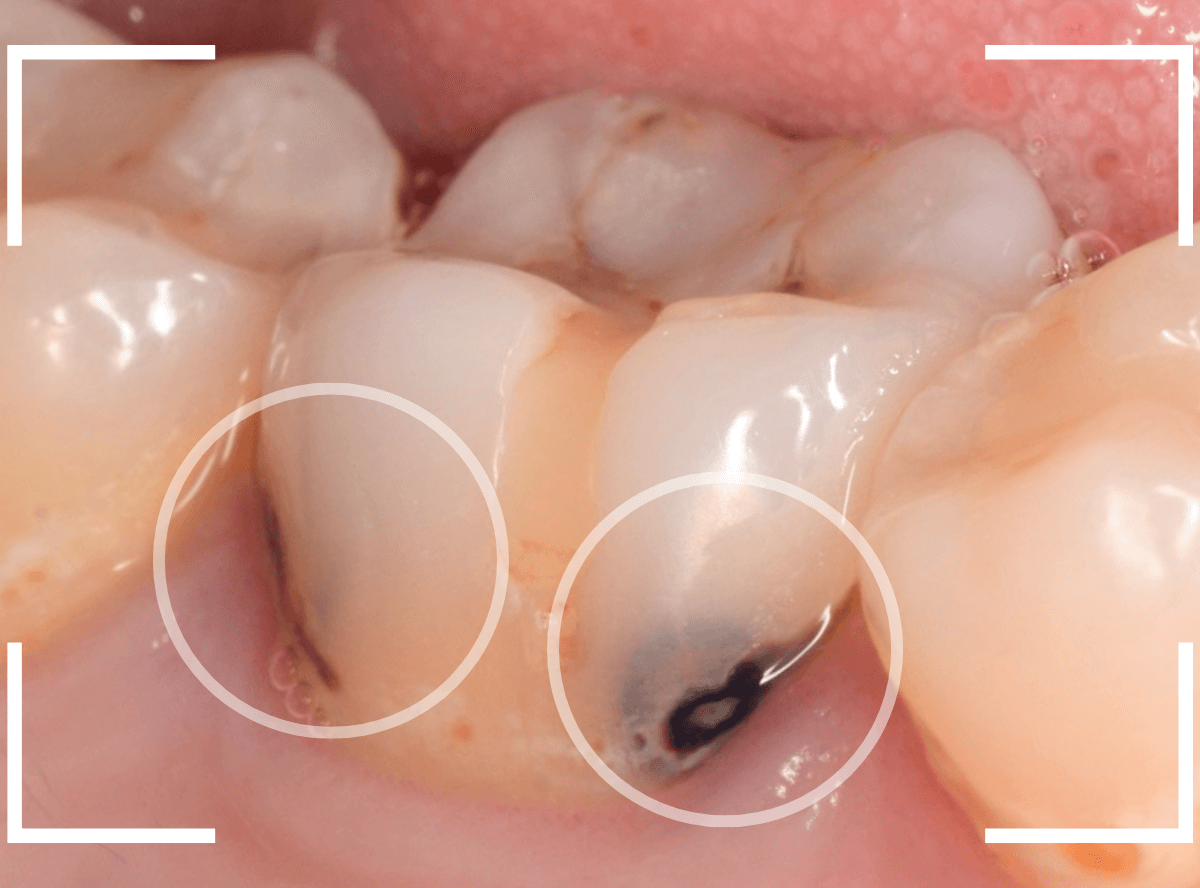

Case.9 レントゲン写真で写らない側面の虫歯

歯の側面が大きな虫歯になってしまった患者さんのケースです。

このように歯の側面が虫歯になった場合、レントゲン写真で虫歯の状況がはっきりわからない事が多いです。

レントゲン写真では、あまり大きな虫歯のようには見えません。

治療を開始します。

歯を少し削ると、すぐに大きな虫歯の穴が出てきました。

さらに虫歯を削ります。

神経に触れてしまいそうなほど、深くて広い虫歯ですね。

全ての虫歯を除去したところです。

何とか神経に触れる寸前のところで踏みとどまれましたが、レントゲン写真からは想像できない虫歯の深さでした。